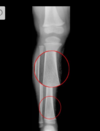

Cisto ósseo simples com fratura

Lesão litica unicameral.

Localização: úmero proximal e femur (< 20 anos) ou calcâneo, talus, ileo (> 20 anos).

Se fratura: Sinal do fragmento caído.